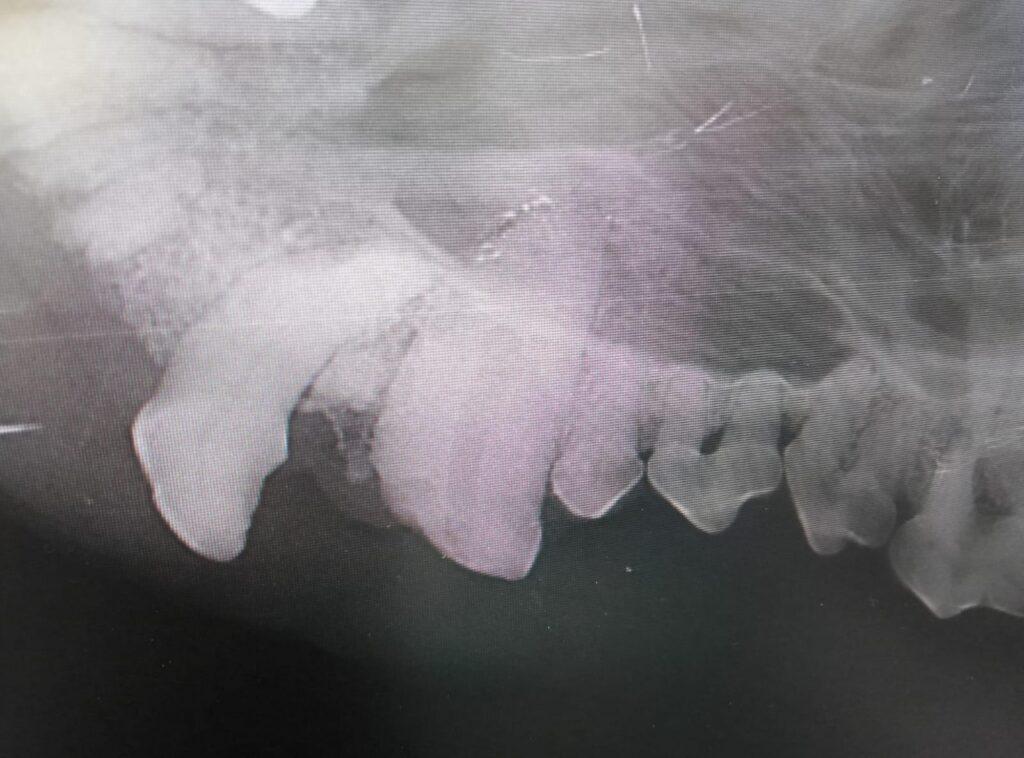

Liebe PfotenFreunde, Mirto hat seine Zahn-OP erfolgreich über die Bühne gebracht. Die OP war sehr aufwendig. Zuerst wurde eine Zahnreinigung gemacht. Danach wurden dem kleinen Mann 12 Zähne gezogen, ein Zahn war gebrochen und musste heraus operiert werden. Außerdem stellte man bei der OP fest, dass Mirto eine starke Parodontis hat, die man bei der Gelegenheit auch gleich mit behandelt hat.

Mirto, unser kleiner Kämpfer, wird derzeit mit viel Liebe in einer Pflegestelle in Bonn umsorgt, während er auf sein endgültiges Zuhause wartet. Doch jetzt steht er vor einer neuen Herausforderung: Er hat starke Zahnschmerzen und kann kaum noch alleine fressen.

Die Tierärztin hat bestätigt: Er braucht dringend eine Zahnsanierung – und zwar so schnell wie möglich, damit er endlich schmerzfrei leben kann.